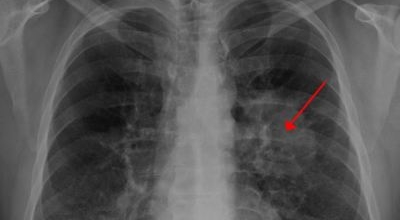

폐암 검사는 X-ray를 통해서 검사하는데 , 크기가 작거나 구석에 위치한 경우 확인이 어려운 경우도 있습니다. 그리고 조직 검사를 통해서 정확한 진단을 하게 돼요. 폐암이 발견되면 종양의 크기나 전이 여부 , 위치에 따라서 수술 여부를 결정하게 되어요.